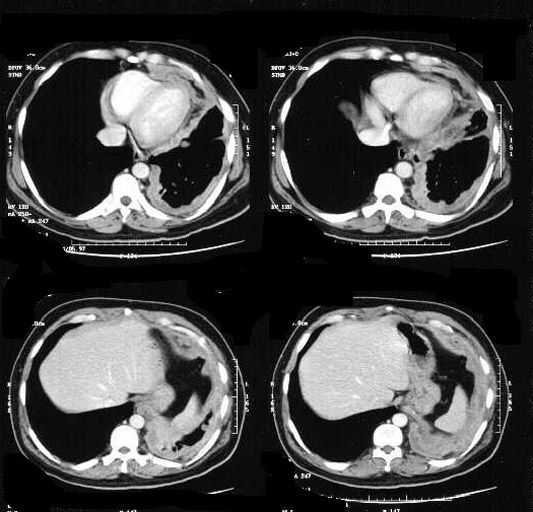

CT showing pleural mass encircling lung.

Mesothelioma